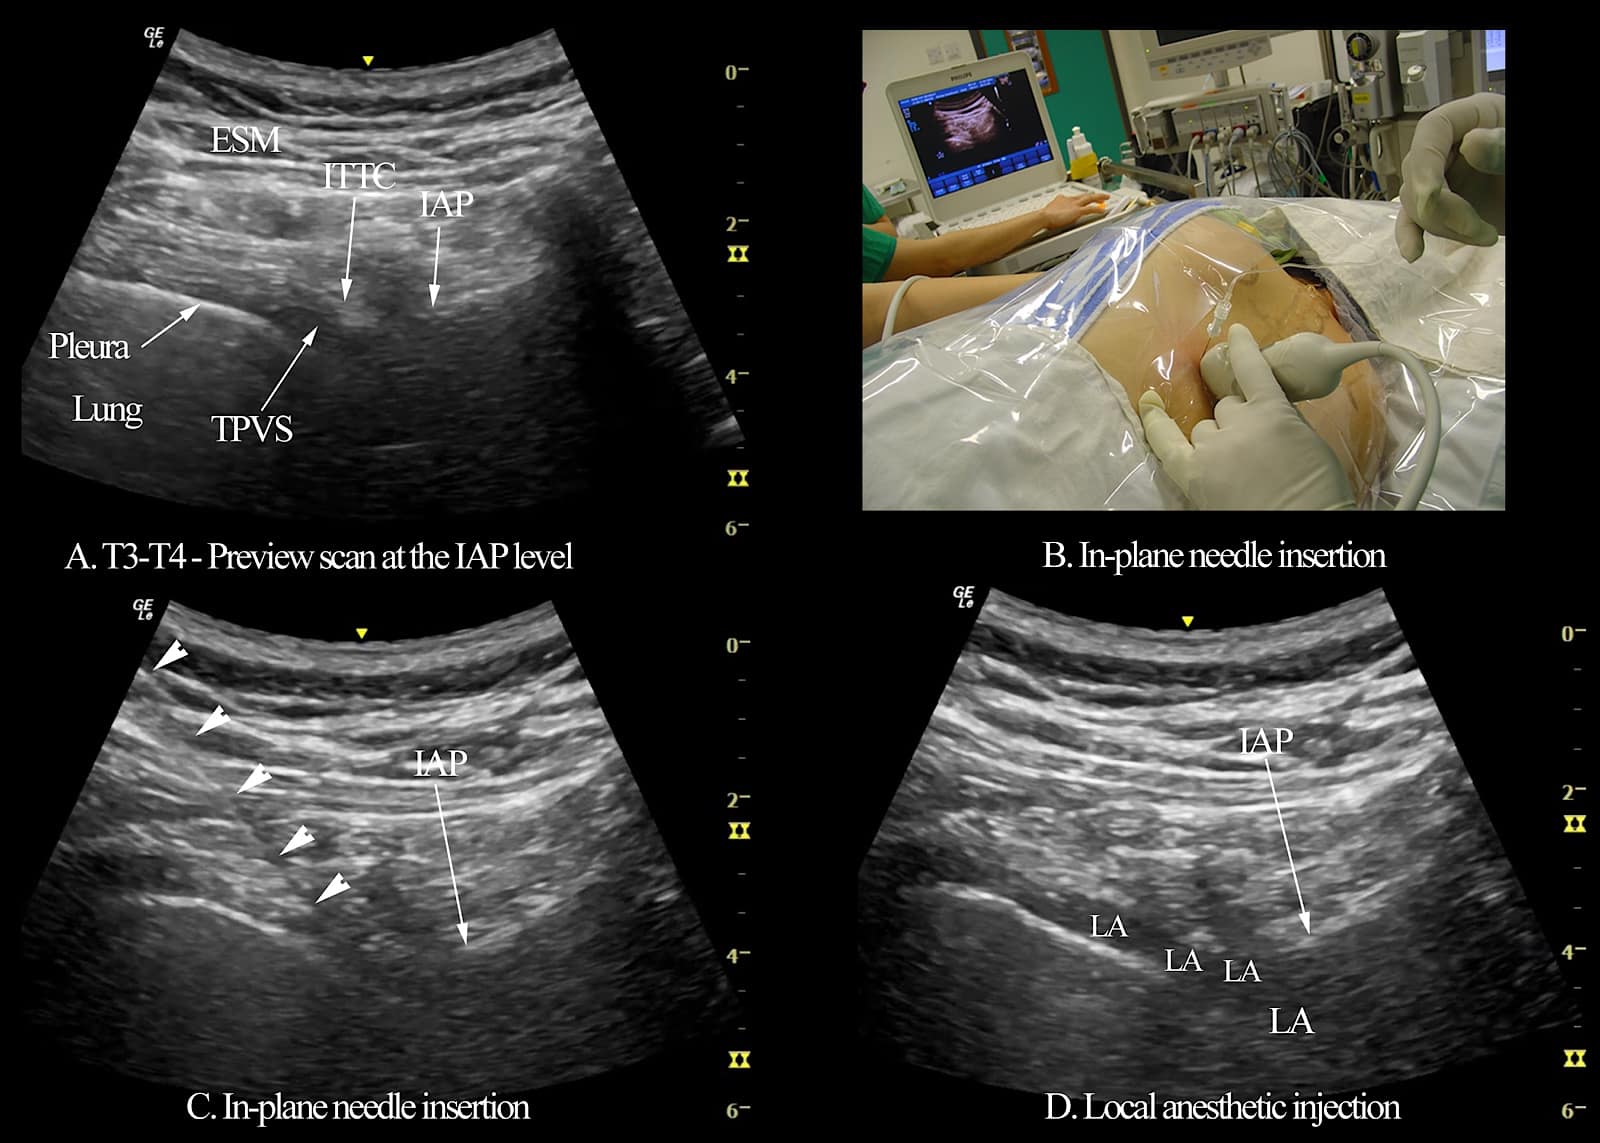

Figure 8. A series of images illustrating ultrasound-guided thoracic paravertebral block (TPVB) using a transverse scan at the inferior articular process (IAP) level, including the target transverse sonogram at the IAP level (A), the position of the patient and orientation of the curvilinear ultrasound transducer (B), in-plane needle insertion with white arrowheads showing the path of the block needle (C), and widening of the paravertebral space and spread of the local anesthetic to the posterior intercostal space (D).

TPVS = thoracic paravertebral space, ITTC = intertransverse tissue complex, ESM = the erector spinae muscle

Reproduced with permission from the Department of Anesthesia and Intensive Care, The Chinese University of Hong Kong, Faculty of Medicine, www.aic.cuhk.edu.hk/usgraweb.

USG TPVB Using the Transverse In-plane Approach at the IAP Level

Under strict aseptic precautions, and with the target transverse ultrasound window at the IAP level in view (Figure 8), the nerve block needle is introduced in-plane from a lateral-to-medial direction (Figure 8B).11,62,63 The needle is advanced under real-time ultrasound guidance with a gentle back-and-forth (jiggling) motion until the needle tip is embedded within the ITTC. Interestingly, it is not uncommon to lose track of the needle tip once it enters the ITTC, possibly because the needle and ITTC are isoechoeic (Figure 8C). The needle is advanced in small increments followed by a 1-2 ml of 0.9% saline test bolus. Swelling of the ITTC or an anechoic fluid-filled area within the ITTC indicates that the needle tip is still within the ITTC. Entry of the needle tip into the TPVS is visualized as anterior displacement of the parietal pleura, widening of the paravertebral space, and increased pleural echogenicity upon saline injection (Figures 8D and 13).11,62,63 A calculated dose of LA is then injected in small aliquots.11,62-64 For multi-level USG TPVB, such as for primary breast cancer surgery, we use 3-4 ml of 0.5% ropivacaine or levobupivacaine with 1:200,000 epinephrine per level, with the total volume capped at 25 ml (125 mg) for the 6 injections (T1-T6).11,62,63 For perioperative analgesia, 20-25 ml of the same LA is injected at a single-level (T3-T4 for PBCS).64